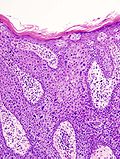

|

Squamous cell carcinoma. H&E stain. | |

Squamous cell carcinoma of the skin is a common malignant neoplasm of the skin.